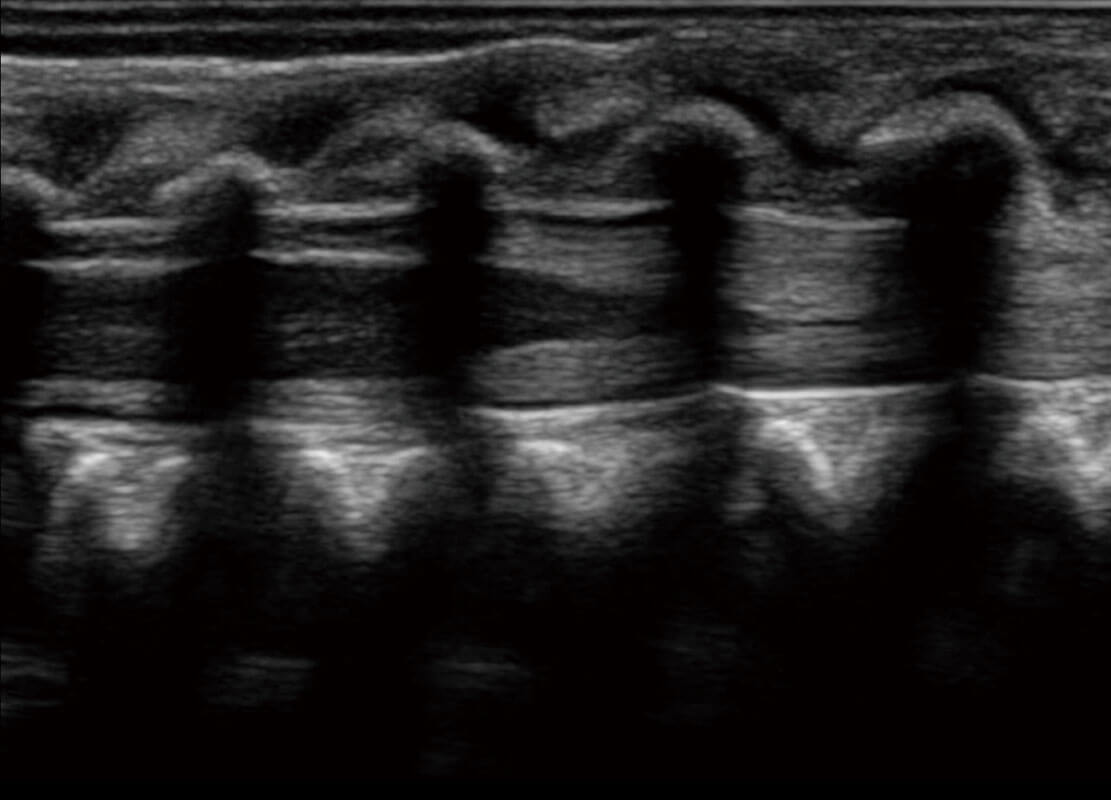

胎心筛查

P60搭载一系列胎儿心脏成像技术,实现精细的胎儿心脏评估。

• 四腔切面

• 四腔心血流

• 右室双出口

• 胎心容积成像